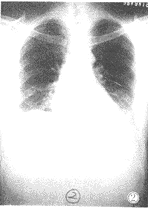

②局限在肺的一段或一叶内的片状或大片状模糊阴影,密度不均,边缘模糊,以中下肺野多见,类似大叶性肺炎或肺段肺炎。本组有13例,占16.7%(图2)。

图2 节段实变型:表现左下肺野心缘旁片状模糊密度增高影,局限在左肺上叶舌段水平。